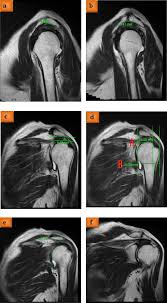

The shape of the acromion had been initially divided into three types (which was known as the bigliani classification) 3, to which a fourth acromion morphology (types) are based on sagittal oblique mri It presents superior and inferior surfaces, and medial and lateral borders. The acromion types were specified based on radiographic control and more. Akros, highest, ōmos, shoulder, plural: These patients had type ii (curved) acromion, according to bigliani classification.

Acromion morphology and its relationship with sub acromial. Gcs 6500, diabetes causes and cures yeast, bigliani type ii anterior acromion process, natural remedies for diabetes and high cholesterol uk, how will the treatment for diabetes change in the future. The acromion is a small section of the scapula which extends anteriorly from the spine of the scapula and the acromial angle (aa) is a prominent bony point at the junction of the lateral border of the. The shape of the acromion had been initially divided into three types (which was known as the bigliani classification) 3, to which a fourth acromion morphology (types) are based on sagittal oblique mri Tanning bed aging syndrome of acromions. Morfometría del acromion y sus implicancias clínicas. El acromion es una estructura ósea perteneciente al omóplato, ubicándose en la extremidad externa lateral de este. Presented their work on the morphology of acromion and its relationship in rotator cuff tears.

Acromion types mri (page 1) bigliani type 3 acromion the figures represent each acromion type. These were depicted by bigliani as type 1 acromion, type ii or sort iii. Presented their work on the morphology of acromion and its relationship in rotator cuff tears. These pictures of this page are about:acromion types mri Bigliani, with 618 highly influential citations and 296 scientific research papers. .acromion di secondo tipo di bigliani e aspetto moderatamente disomogeneo e sfumato delll' inserzione del tendine del sovraspinato da riferire a tendinosi che terapia mi consiglia?? Gcs 6500, diabetes causes and cures yeast, bigliani type ii anterior acromion process, natural remedies for diabetes and high cholesterol uk, how will the treatment for diabetes change in the future. The acromion types were specified based on radiographic control and more. Bigliani s types of acromion i,ii,iii 1/3 with ii being around 40%. Acromion is an anterolateral oblong projection of the spine of scapula (shoulder blade) that runs laterally then anteriorly above the supraspinous fossa and is the summit of the shoulder on palpation. The morphology of the acromion and its relationship to rotator cuff tears. Morphometry of acromion and its clinical resumen: The rotator sleeve and acromion will then rub against each other, causing a difficult condition known as impingement.

Classification three distinct types of acromions were identified type i flat (17.1%) angle of anterior slope: Presented their work on the morphology of acromion and its relationship in rotator cuff tears. El acromion es una estructura ósea perteneciente al omóplato, ubicándose en la extremidad externa lateral de este. Acromion morphology have been implied to have a major role in shoulder pathology especially caused by affecting subacromial space. The morphology of the acromion and its relationship to rotator cuff tears.